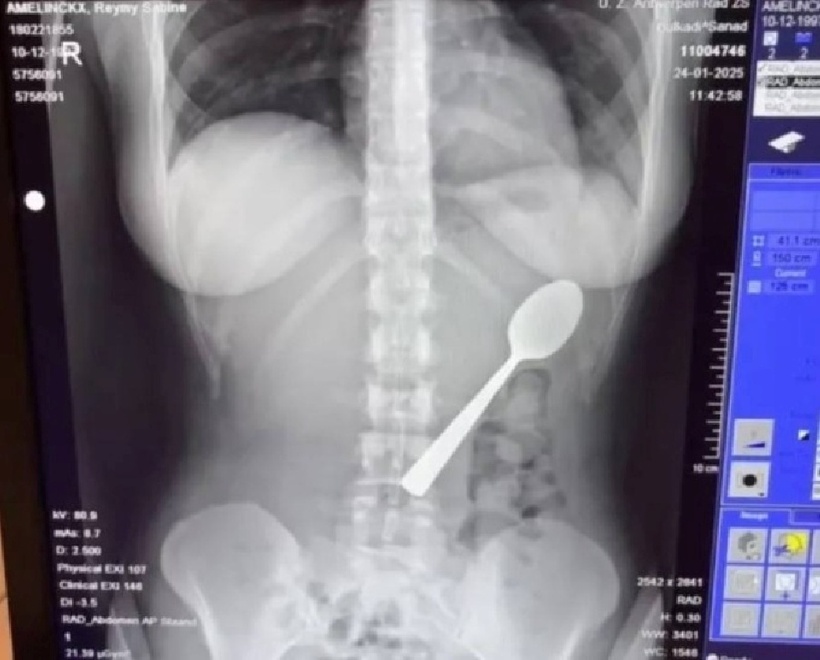

Một phụ nữ tại Bỉ đã gặp sự cố hy hữu khi vô tình nuốt trọn chiếc thìa dài 17 cm, sau lúc chó cưng bất ngờ nhảy lên người trong lúc cô đang ăn sữa chua.

Trong tình huống bất đắc dĩ, Reymy cho biết cô buộc phải lựa chọn giữa việc bị nghẹn hoặc nuốt hẳn chiếc thìa. Cuối cùng, cô chọn phương án thứ hai và cảm nhận rõ chiếc thìa trượt xuống dạ dày “một cách khá trơn tru”.

"Lúc đó tôi không cảm thấy gì cả nên tôi không nói gì ngay. Mãi đến sau bữa tối tôi mới nhận ra chuyện đó thực sự khá nghiêm trọng. Có một chiếc thìa dài 17cm trong dạ dày tôi. Trên mạng, ai cũng nói giống nhau: hãy đến thẳng phòng cấp cứu. Chỉ đến lúc đó tôi mới nhận ra nó nguy hiểm đến mức nào", Reymy nói thêm.

Theo Người đưa tin, các bác sĩ nói với cô rằng chiếc thìa quá lớn để có thể tự trôi ra ngoài, vì vậy cô phải về nhà và chờ đến khi có thể lên lịch nội soi dạ dày. Reymy nói: "Đêm đó thật khó khăn, tôi cảm thấy chiếc thìa di chuyển, đôi khi thậm chí còn kẹt giữa các xương sườn của tôi. Thật sự rất kinh khủng.

Hai ngày sau, dụng cụ đó được lấy ra dưới gây tê cục bộ.